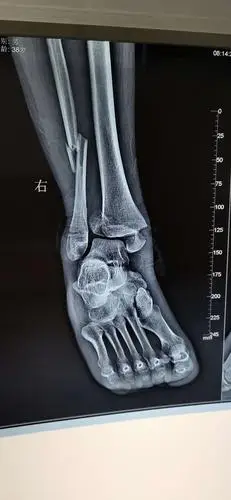

一例胫腓骨远端骨折下胫腓联合分离病例